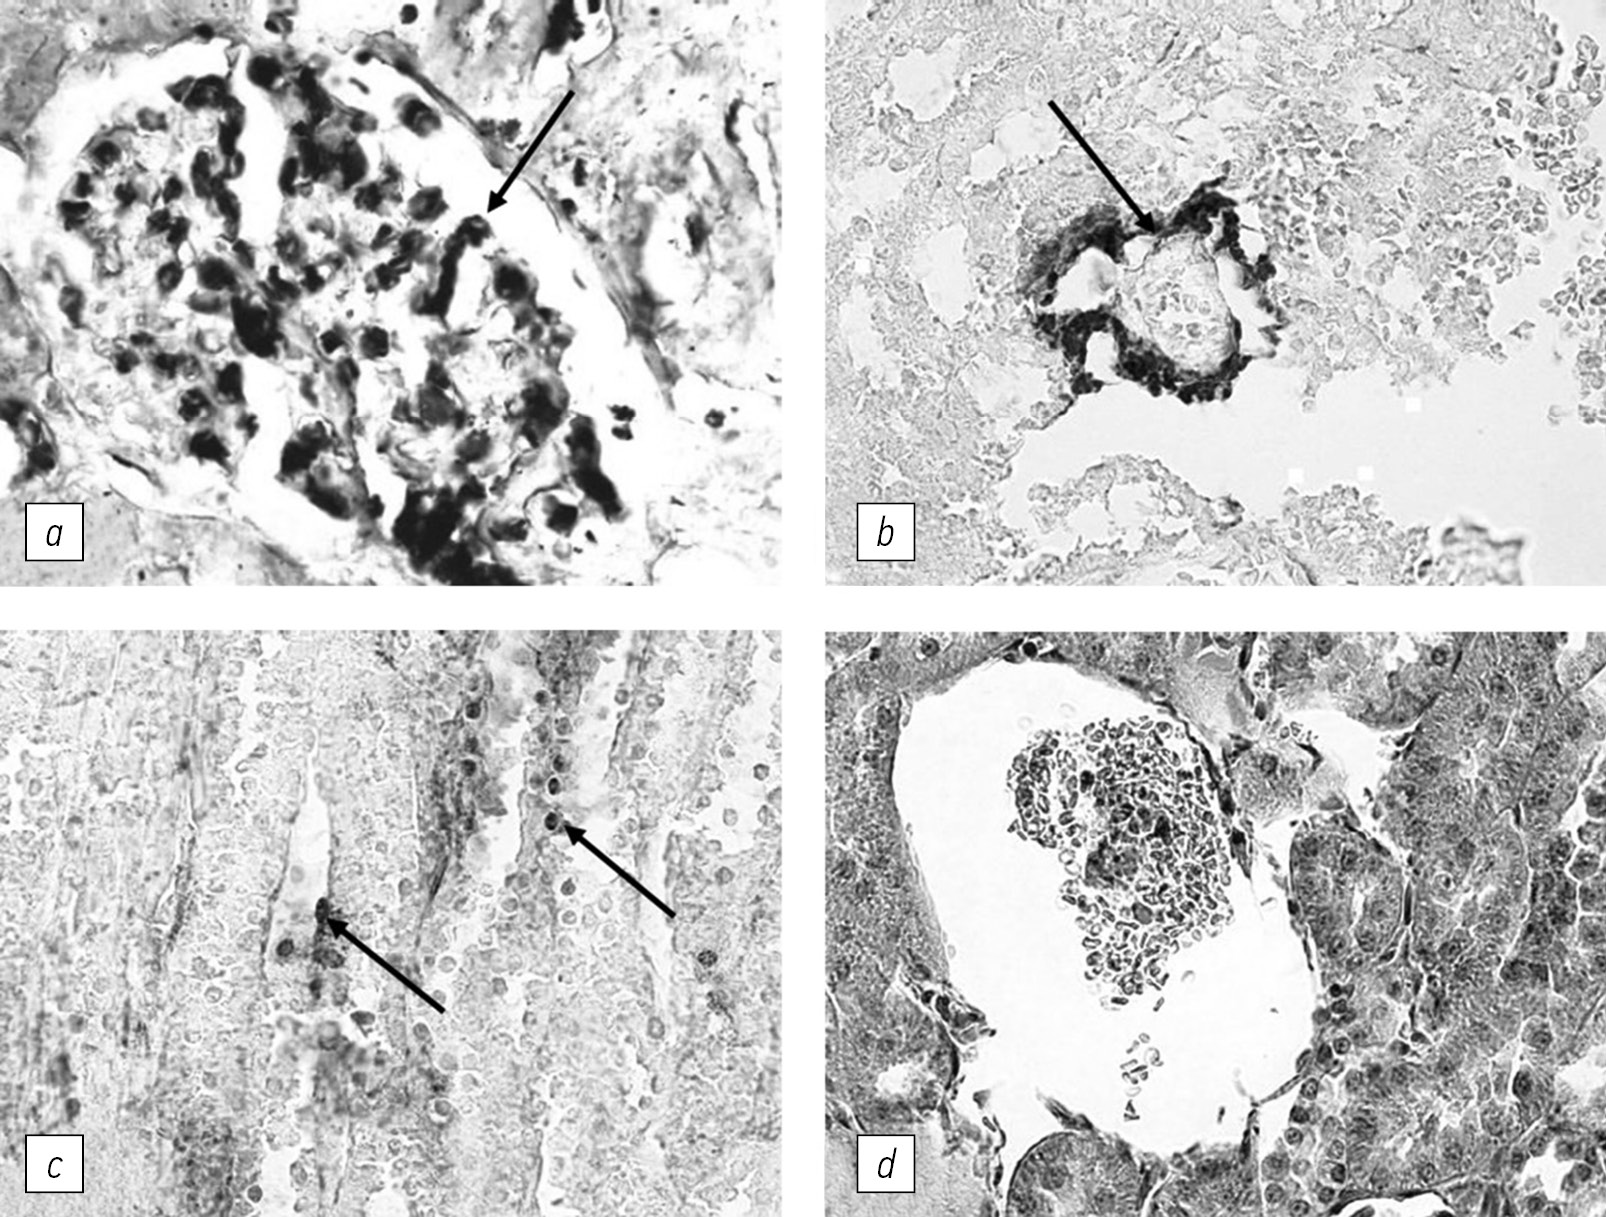

Fig. 1. Immunomorphological changes in cortical and medullary layers of the rabbit kidney, induced by Streptococcus pyogenes strain emm12 [43]: a — the expression of TNF-α by glomeruli mesangial cells (arrow); b — IgG deposition in the wall of the proximal tubule (arrow); c — deposition of C3 component of complement in the cells of the distal tubules (arrows); d — atrophy of the tissues of the renal glomeruli, the abundance of red blood cells in the cavity. a–c — immunohistochemical staining, ×750; d — staining with hematoxylin-eosin, ×550

To model glomerulonephritis in rabbits, we administered heat-killed cells of GAS types M1, M4, M15, and M22 that bind to the Fc fragment of native IgG, as well as type M12 that binds to immune complexes (Table 2). It has been shown that after binding of IgG by streptococci, antibodies specific to rabbit and human IgG are produced in rabbits. The blood of experimental animals showed the presence of anti-IgG antibodies in titers ranging from 1:80 to 1:640, depending on the time of sampling and individual characteristics of the rabbits. Glomeruli showed deposits of IgG and complement component C3. These deposits were accompanied by an increase of pro-inflammatory cytokines, such as IL-1β, TNF-α, and IL-6, and infiltration of tissues by lymphocytes/macrophages, eventually leading to the formation of local immune inflammation, with subsequent degeneration and destruction of the tissue. The process culminated in the development of membranous-proliferative glomerulonephritis, with some variability in the dynamics of morphological changes in individual rabbits (Fig. 1 and 2).